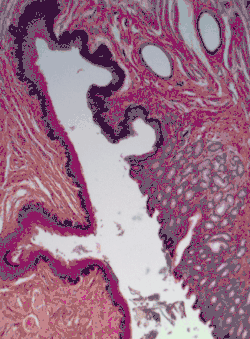

[Micrograph] of normal stratified squamous epithelium and the metaplasic epithelium of Barrett's esophagus (left of image). Alcian blue stain. -